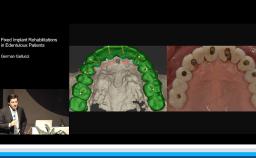

Esthetically challenging cases often involve two or more specialized clinicians working together throughout the treatment phases. This step-by-step cooperation is crucial to arriving at a pleasing esthetic result. This lecture presents various situations of compromised teeth and implants in which an interdisciplinary approach and modification are indicated. The rationale for predictable treatment and some clinical tips are also discussed.